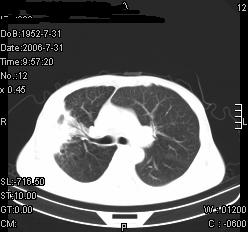

患者,男,54岁,咳嗦,咳痰20天。抗炎治疗2周。现esr76mm/h,目前患者症状明显好转,但发现两次ct片未见明显变化。两次分别做与7.25、7.31。第一次诊断右肺上叶炎症累计胸膜。大家看,从影像上内排除结核吗?

结核的可能性非常大,右上肺病变应该考虑干酪性肺炎。理由:

1.纵隔内多发淋巴结肿大。

2.esr76mm/h。

3.虽经抗炎治疗肺窗病灶有所吸收、减小,但纵隔窗病灶形态、密度、范围无明显变化。如果是单纯的大叶性肺炎,“抗炎治疗2周,目前患者症状明显好转”病灶应该基本消散了,至少也处于吸收消散期,密度变淡、范围变小。同时本病例所示其内的密度不均匀,见多发大小不一空洞样影也不符合大叶性肺炎吸收消散期表现。

病灶特点:片状 索条 结节混杂影,部分融合,密度不均,广泛累及相应胸膜.

临床治疗;二周未吸收.但症状好转.

多考虑:肺结核.